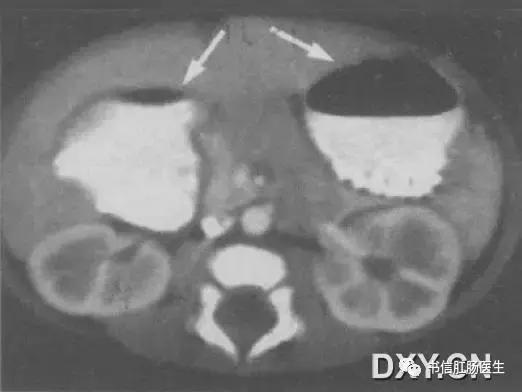

★ 男婴,14 天,CT 上可见「双泡征」(箭),肠系膜上动、静脉排列正常

■ 影像表现:腹部 X 线平片上表现为上腹部出现 2 个含气囊腔样结构,分别位于左上和中线右侧略偏下,立位可见液气平面,远端无充气或仅有少量充气。该征象还可见于上消化道钡剂或超声检查。

■ 征象解析:双泡征是新生儿或婴儿十二指肠梗阻的特异性表现。十二指肠梗阻时,梗阻近端的十二指肠和胃呈进行性积气、积液并扩张,形成所谓的双泡征。

■ 讨论:双泡征多见于十二指肠闭锁,也可见于十二指肠狭窄、环状胰腺或肠旋转不良等。根据双泡征及其伴随征象可大体判断梗阻的程度及原因,若双泡较大且远端充气,则提示十二指肠完全梗阻(十二指肠闭锁);双泡较小且远端有或多或少的充气,则多为不全梗阻(肠旋转不良、十二指肠狭窄、环状胰腺等)。

另外,当不全性梗阻因气体未进入梗阻远端或梗阻远端少量充气被肠壁吸收,可表现为单纯的双泡征。另一方面,当双泡征远端肠管充气时,并不能排除完全梗阻的可能,因十二指肠闭锁合并胆管发育异常时,梗阻近端气体可通过异常胆管进人梗阻远端。因此,在判断十二指肠梗阻程度时,不能依赖于梗阻远端有无充气。而应全面观察,综合分析,必要时行钡剂或超声检查。